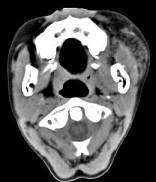

问题 男,12岁,左面颊肿大5年余,局部呈紫红色,CT如图所示,最可能诊断为()

选项 A.蔓状血管瘤 B.血管外皮瘤 C.动静脉畸形 D.慢性腮腺炎 E.下颌下腺慢性炎症

答案 A